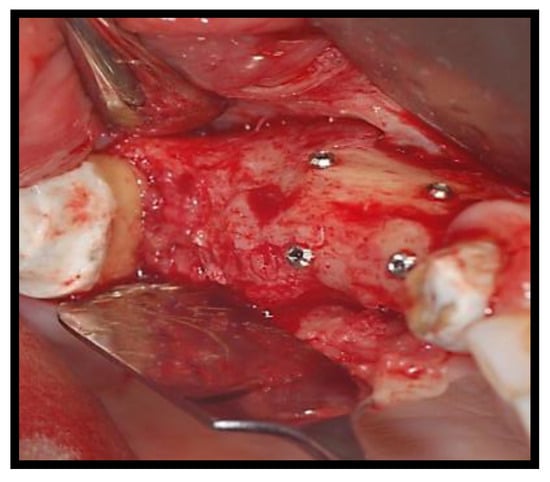

2.1. Surgical Procedures